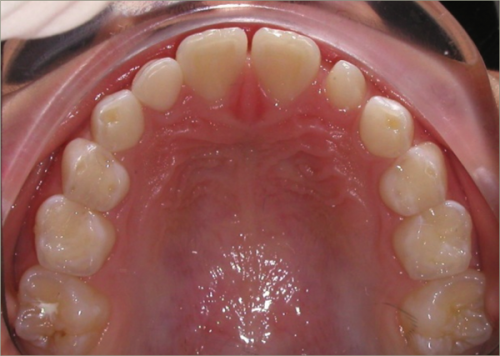

12 year old female:

Diagnosis:

- Missing upper right lateral incisor & lower right cuspid

- Horizontally impacted lower left cuspid

- Peg shaped upper left lateral incisor

Treatment:

- Extraction of impacted lower left cuspid, and peg shaped upper left lateral incisor

- Upper cuspids substituted as laterals

- Full fixed appliances

- 20 months